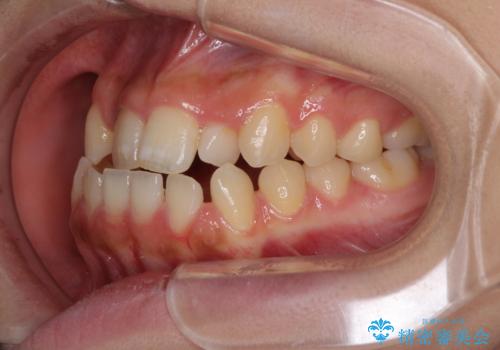

- 前歯のデコボコと、下顎の変位と受け口を気にして来院された患者様です。

初診時には大学病院にて顎の骨を切る外科矯正を勧めましたが、妥協的なゴールでも構わないので外科処置をせずに矯正を行いたいとのことでした。

まずは急速拡大装置にて上顎骨を側方に拡大し、インビザラインにて歯列と咬合を整えることとしました。

上顎骨を拡大したことで、下顎の歯列を上顎が受け入れられるようになりましたが、インビザラインでは咬み合わせを改善させることができなかったため、ワイヤー矯正にて仕上げることとしました。